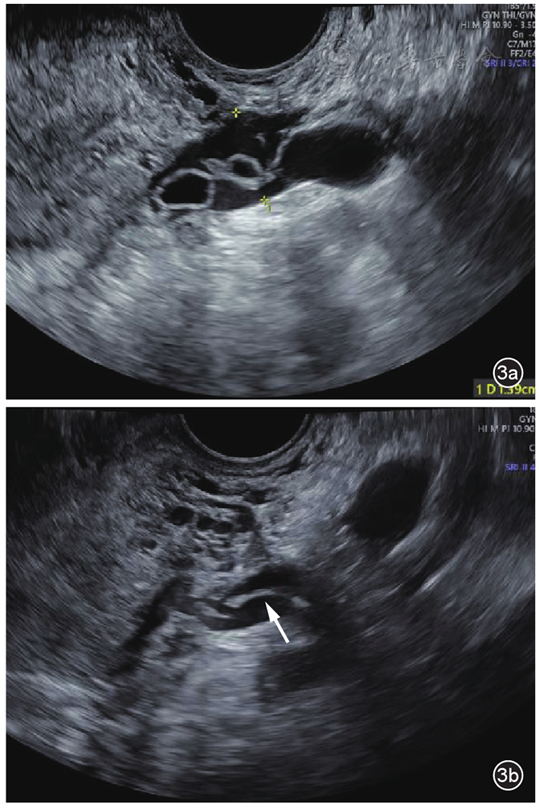

图3 盆腔静脉侵袭性葡萄胎患者化疗前、后左侧宫旁静脉病灶变化超声对比图像。图a为化疗前宫旁扩张静脉内可见多个囊泡状无回声;图b为化疗后左侧宫旁静脉扩张较前减轻,管腔内囊泡状无回声消失,仅见少许条索状中等回声(箭头所示)

综合临床表现、实验室检查及影像学特征,临床诊断为高危型妊娠滋养细胞肿瘤Ⅱ期,预后评分7分。患者接受了更生霉素联合拓益(PD-1抑制剂)化疗,共8个疗程。化疗期间,患者血β-hCG水平逐渐降至正常。化疗7个疗程后复查经阴道超声显示左侧宫旁静脉扩张较前明显减轻,较宽处约0.8 cm,其内见少许条索样中等回声,宽约0.2 cm,未见明确囊泡状无回声,余盆腔静脉及髂静脉内未见异常回声(图3);盆腔增强MRI显示左侧附件区多发异常信号及血管流空影较前减小,子宫肌层信号不均较前稍减轻,提示治疗效果显著。本研究经北京协和医院伦理委员会审批同意(批件号:I-24PJ2530)。